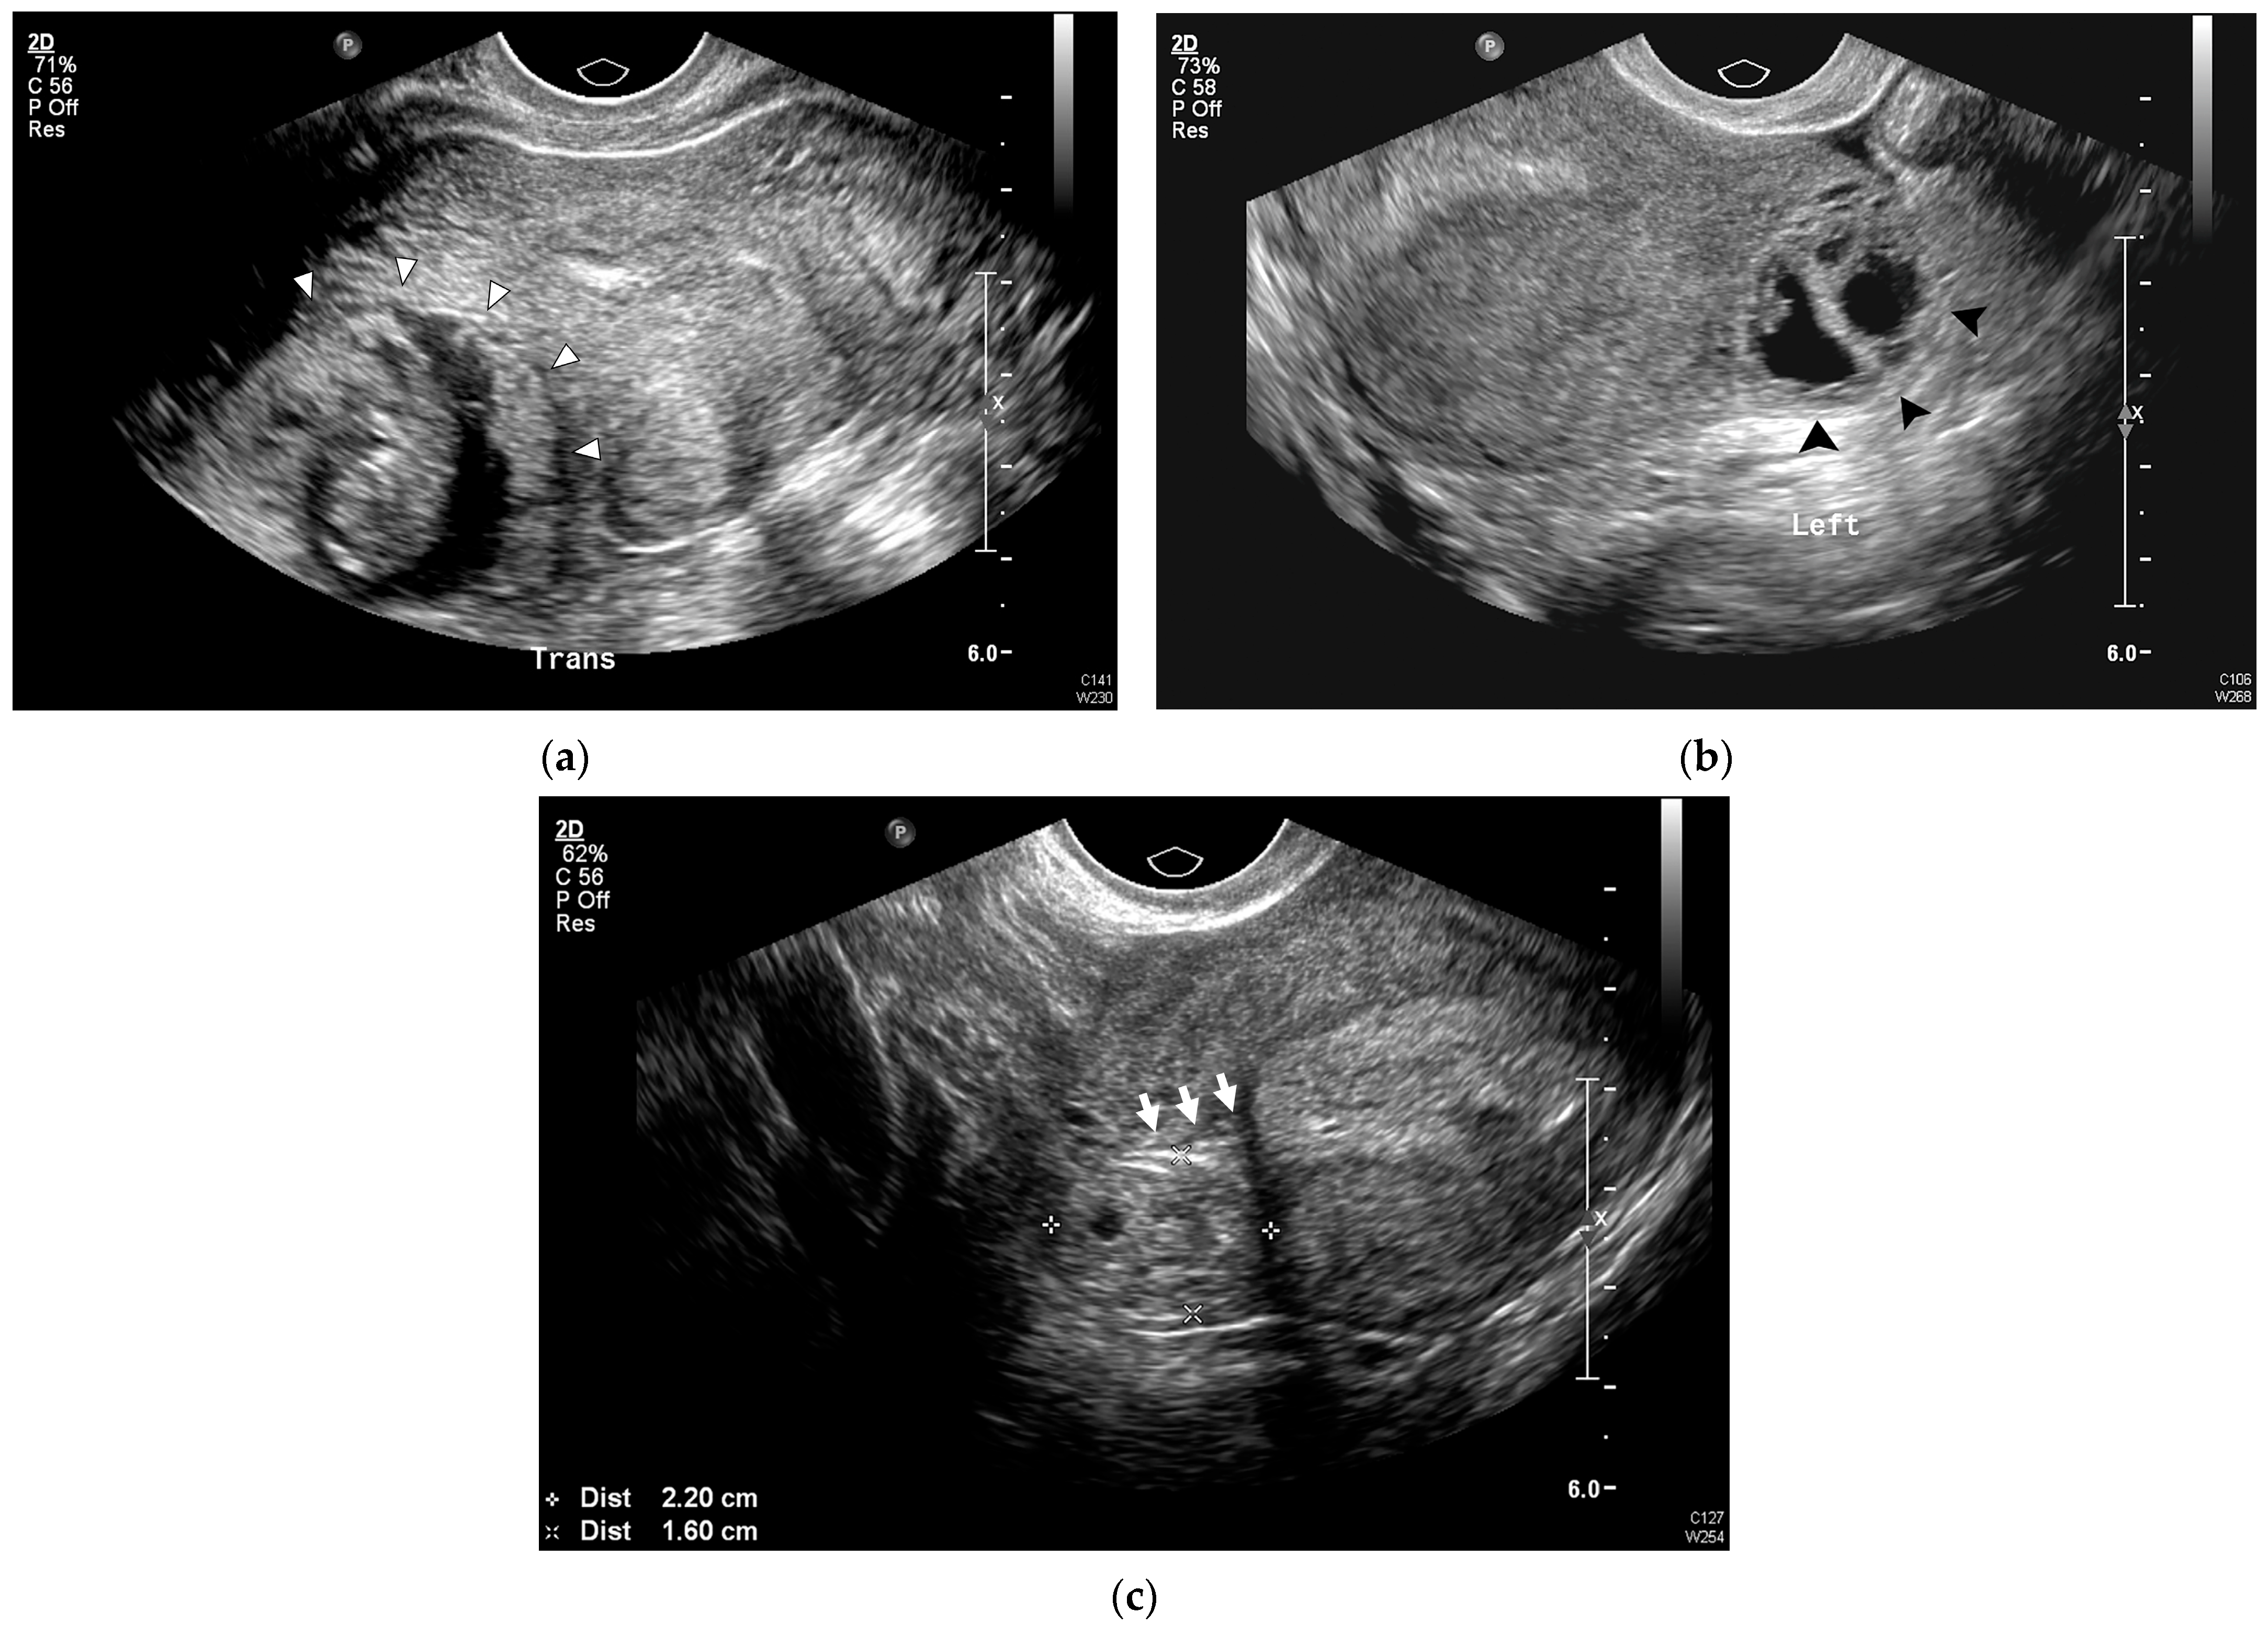

| Eccentrically located GS | 15 (78.9) | 44 (100.0) | 0.010 |

| Absent surrounding endometrium | 0 (0.0) | 40 (90.9) | <0.001 |

| Myometrial thickness (mm) | 6.7 ± 2.5 | 2.6 ± 1.2 | <0.001 |

| Interstitial line sign | 0 (0.0) | 14 (31.8) | 0.014 |